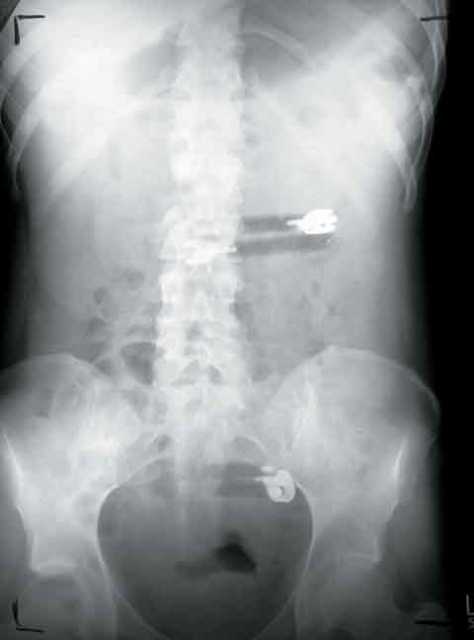

Droga u organizmu, ilustracijaD.E je prije dolaska na Međunarodni granični prelaz Orašje u kondom stavila 23 grama heroina te je kondom gurnula u vaginu. Graničnim policajcima je žena bila sumnjiva te su je odveli dežurnom ginekologu.

On joj je u rodnici našao prezervativ u kojem se nalazila "bijela praškasta materija" koja je podsjećala na heroin. Prvim vještačenjem je utvrđeno da se radi o 23 grama heroina.